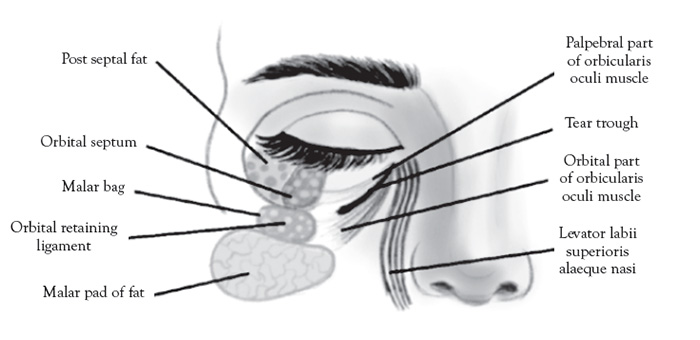

The orbicularis retaining ligament forms the superior border of the nasolabial and medial fat compartments. These two compartments combine to form the malar fat pad, an important structure in midface aging [102]. Elevation and repositioning of the malar fat pad is the primary target for midface aesthetic enhancement [103].

The contents of the eye bag (Figure 5) are an important part of the screening protocol for non-surgical versus surgical blepharoplasty planning in which ultrasound can promising diagnostic utility. The contents of the eye bag (principally the distinction between fluid edema from fat) are equally important to elucidate during the screening procedure. The distinction of periorbital edema and fluid from normal fat can be tricky clinically, but easily elucidated with ultrasound.

Another indication for ultrasound is to address excessive periorbital swelling related to over-correction/over-filling of the tear trough area under the eye using cosmetic filler. This is the result of incorrect placement versus migration of filler above the orbicularis retaining ligament or due to superficial filler placement under the skin [109]. The mechanism of this phenomenon is unclear and difficult to treat clinically [110]. The only solution is to dissolve the filler and then replace the filler using modified (superolateral) technique [111].The orbicularis retaining ligament forms the superior border of the nasolabial and medial fat compartments, which combine to form, collectively, the malar fat pad, a recognized structure affected by midface aging [102]. Cosmetic fillers attempt to rejuvenate the midface by elevating and repositioning the malar fat pad via supraperiosteal injection [103].

Three distinct ultrasound gray-scale appearances can be anticipated in ultrasound screening evaluations of the malar fat pad. Periorbital edema/fluid is anechoic (appears dark on the scans), with posterior wall acoustic enhancement due to low acoustic impedance of water [112]. HA is anechoic to hypoechoic (appears dark to a shade less darker than fluid), a property that is variable, with mixed acoustic impedance, based on the type/viscosity, age of the filler, and degree it has integrated into the surrounding soft tissues [113]. Fat is hyperechoic (appears bright on the scans), due to high acoustic impedance, and easily distinguished from both fluid and HA filler [114].